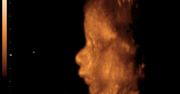

Zdjęcia płodu - twarze

GALERIA